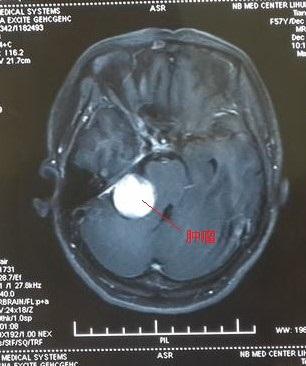

这是MRI增强扫描,图中圆形亮白色为增强的肿瘤